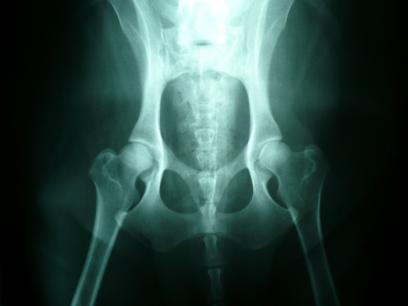

Normal Dog Hips - Good Hip Example - 2013-08-16 15:45:57